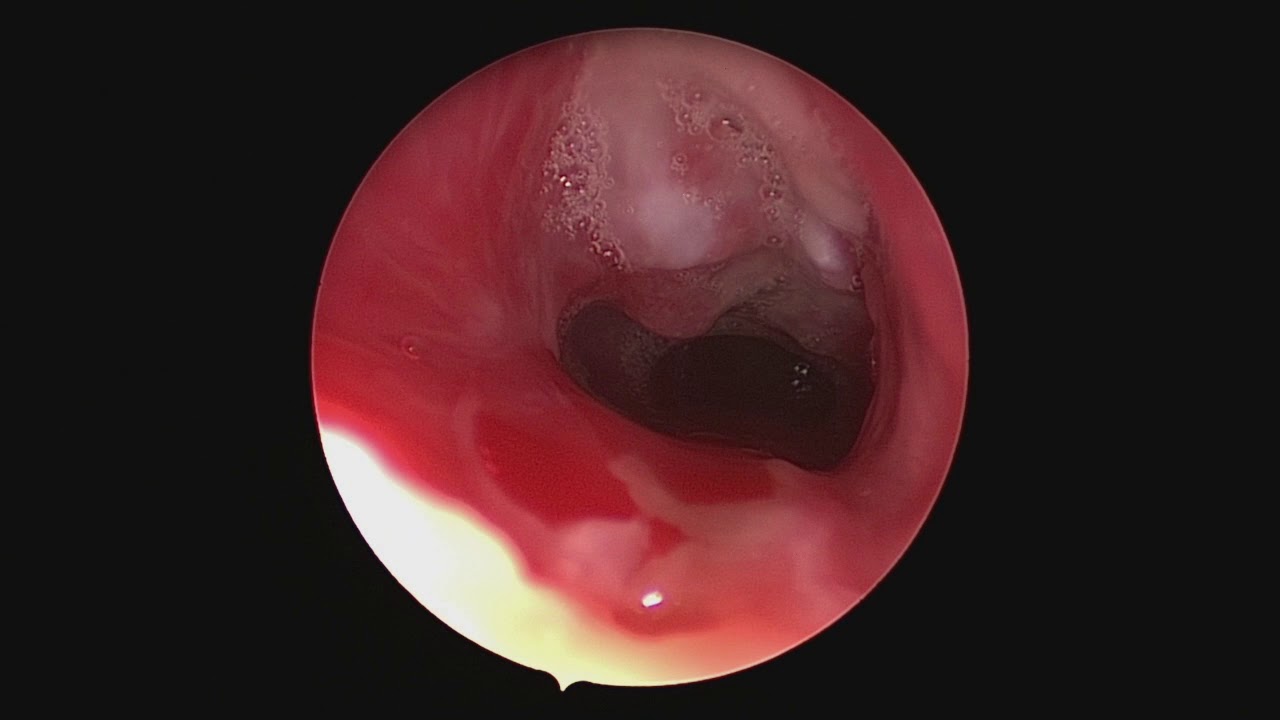

Решающее значение в диагностике стеноза трахеи и бронхов принадлежит эндоскопии дыхательных путей – трахеоскопии, бронхоскопии , в процессе которых есть возможность визуально подтвердить морфологические изменения трахеобронхиальной стенки, уточнить с помощью биопсии этиологию стеноза (рубцовая, опухолевая, туберкулезная). У больных с органическими стенозами трахеи и бронхов исследование ФВД ( спирометрия , пневмотахография ) имеет второстепенное значение (выявляются обструктивные нарушения), однако эти методы широко используются для подтверждения экспираторного стеноза.

Врожденные стенозы крупных бронхов обычно проявляются кашлем и вспышками пневмонии дистальнее сужения и хорошо диагностируются бронхоскопически.